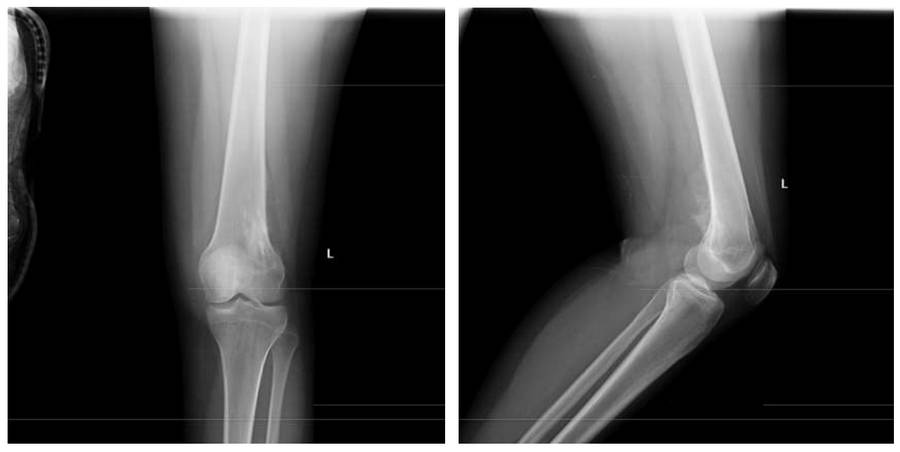

Before the surgeryThe X-ray shows an irregularly bordered mass located laterally in the distal femur, causing bone destruction and extending into the soft tissue.